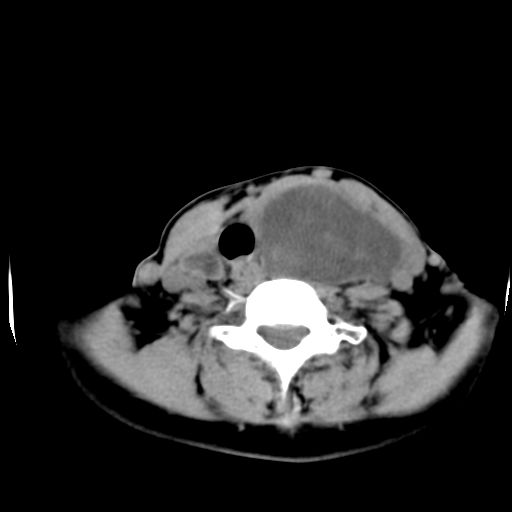

女  53岁  左侧甲状腺肿物3年,近2月明显增大。病理稍后发。

左侧甲状腺内见有一较大类圆形低密度区,边缘清楚光整,增强有一定强化,但仍较正常甲状腺组织强化弱,左侧甲状腺周围组织明显受压移位,且周围组织界限存在,周围组织间隙内未见肿大淋巴结,结合病史考虑为良性病变,左侧甲状腺腺瘤可能大。

左侧甲状腺内见有一较大类圆形低密度区,边缘清楚光整,增强有一定强化,但仍较正常甲状腺组织强化弱,左侧甲状腺周围组织明显受压移位,且周围组织界限存在,周围组织间隙内未见肿大淋巴结。

考虑:甲状腺囊腺瘤

左侧甲状腺内见有一类圆形低密度区,边缘清楚光整,可见明显增强,间隔亦可见增强,且与周围组织分解清晰,周围组织间隙内未见肿大淋巴结。右侧亦可见类似表现。考虑甲状腺腺瘤。

手术病理证实:双侧腺瘤样甲状腺肿。